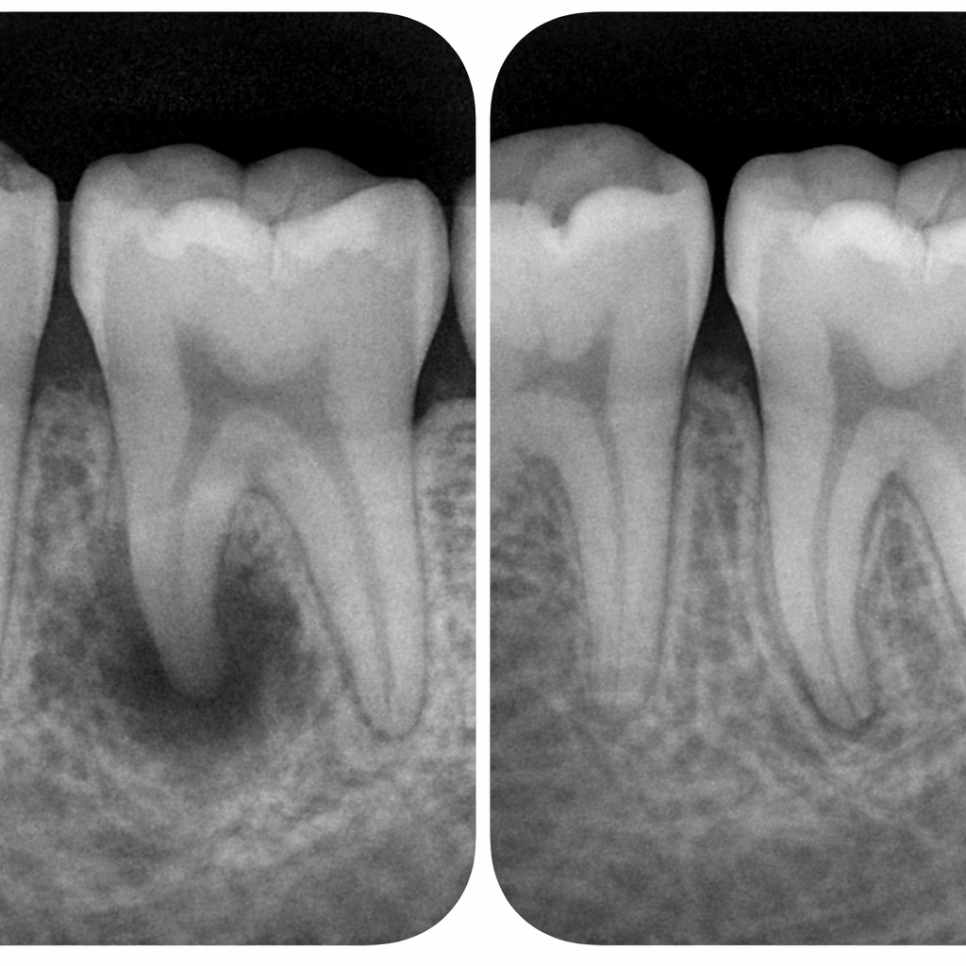

치아 뿌리 끝에 심한 고름 주머니가 있거나,

잇몸 전체가 붓고 피나는 급성 치주염 상태라면

즉시 식립이 어렵습니다.

염증이 심한 상태에서 무리하게 심으면

뼈와 붙지 못하고 탈락할 위험이 큽니다.

임플란트가 식립 직후 흔들리지 않고

안정적으로 고정될 수 있어야 됩니다.

초기 고정력이 충분해야

보철물을 올리기 전까지

임플란트가 흔들리지 않습니다.